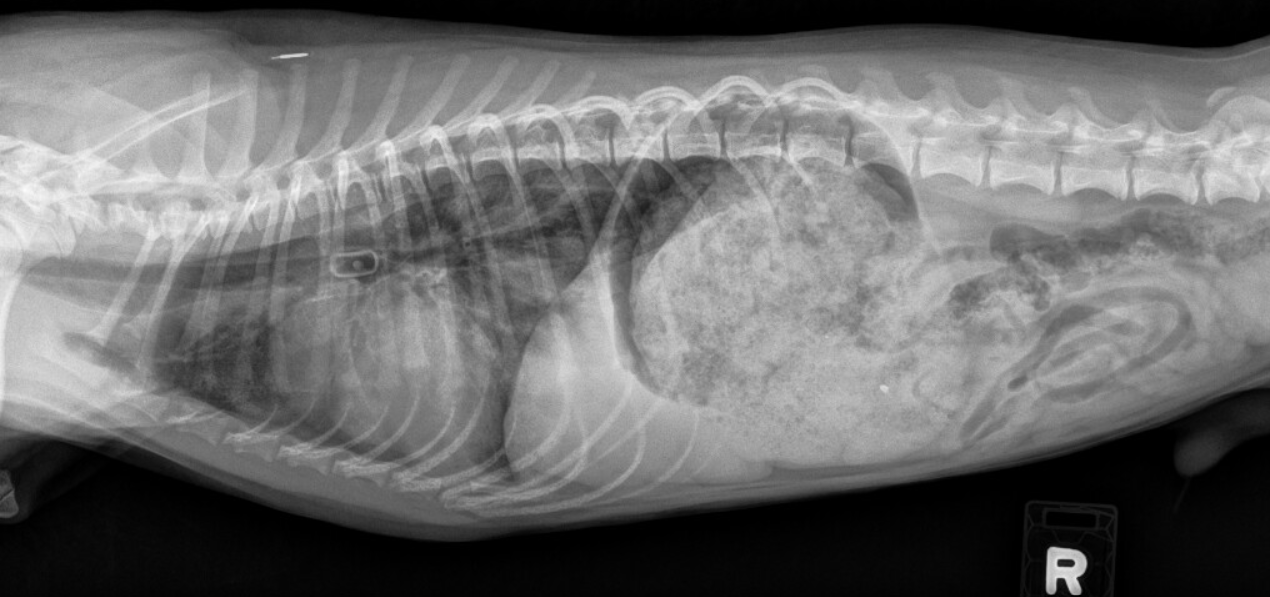

Radiographic Case Study Syncope and choking episode in a young dog Can Syncope Kill A Dog In some cases seizures or syncope can lead to. There are other similar medical causes that result in fainting for both humans and animals. — fainting or syncope is defined as loss of consciousness accompanied by loss of postural tone for a short. Just like in humans, when a dog experiences an episode of fainting, it can be so. Can Syncope Kill A Dog.